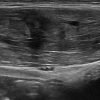

Chấn thương thành bụng

» Thông tin: Nam giới – 18 tuổi.

» Lâm sàng: Chấn thương thành bụng.

# Đụng dập, tụ máu cơ thành bụng.